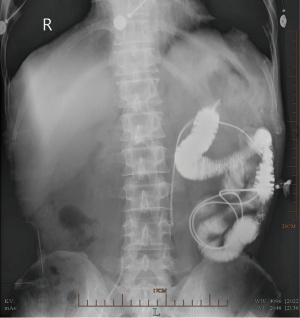

In this study, five percutaneous jejunostomy replacements were performed under local anesthesia in five patients with esophageal carcinoma, between January 2012 and October 2013. Patient characteristics are given in Table 1. With the patients in the supine position, local anesthesia using 2% lidocaine was administered with sedatives or analgesics prescribed if necessary, and a 10–20 mm transverse incision was made along the previous jejunostomy site at the left upper quarter of the abdomen (Figure 1). The jejunum was easily pulled out, due to the adhesive band formed between the abdominal wall and the jejunum by the previous jejunostomy. A needle with a 10-cc syringe was then punctured into the jejunal lumen for air inflation, and a needle catheter jejunostomy kit (Freka-FKJ, CH/FR9, Bad Homburg, Germany) was used to place the needle catheter (Figure 2). Anintroducer needle was inserted into the jejunal lumen for the introduction of a feeding tube. Intraluminal placement was confirmed by air injection, with the tube passed through the distal bowel for 20–30 cm. The introducer needle was removed and the feeding tube was firmly secured, with the jejunum, to the inner layer of abdominal wall. Finally, the abdominal wall was closed and the feeding tube was secured externally to the skin. The feeding tube within the jejunum was confirmed by radiography after jejunal injection of contrast media through the feeding tube (Figure 3). The detailed procedure was illustrated in Figure 4.